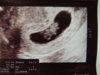

A tutaj z dziś :) 8 tydzień 4 dzień :) 18 mm szczęścia i pięknie bijące serduszko :)

DSCN0732.jpg